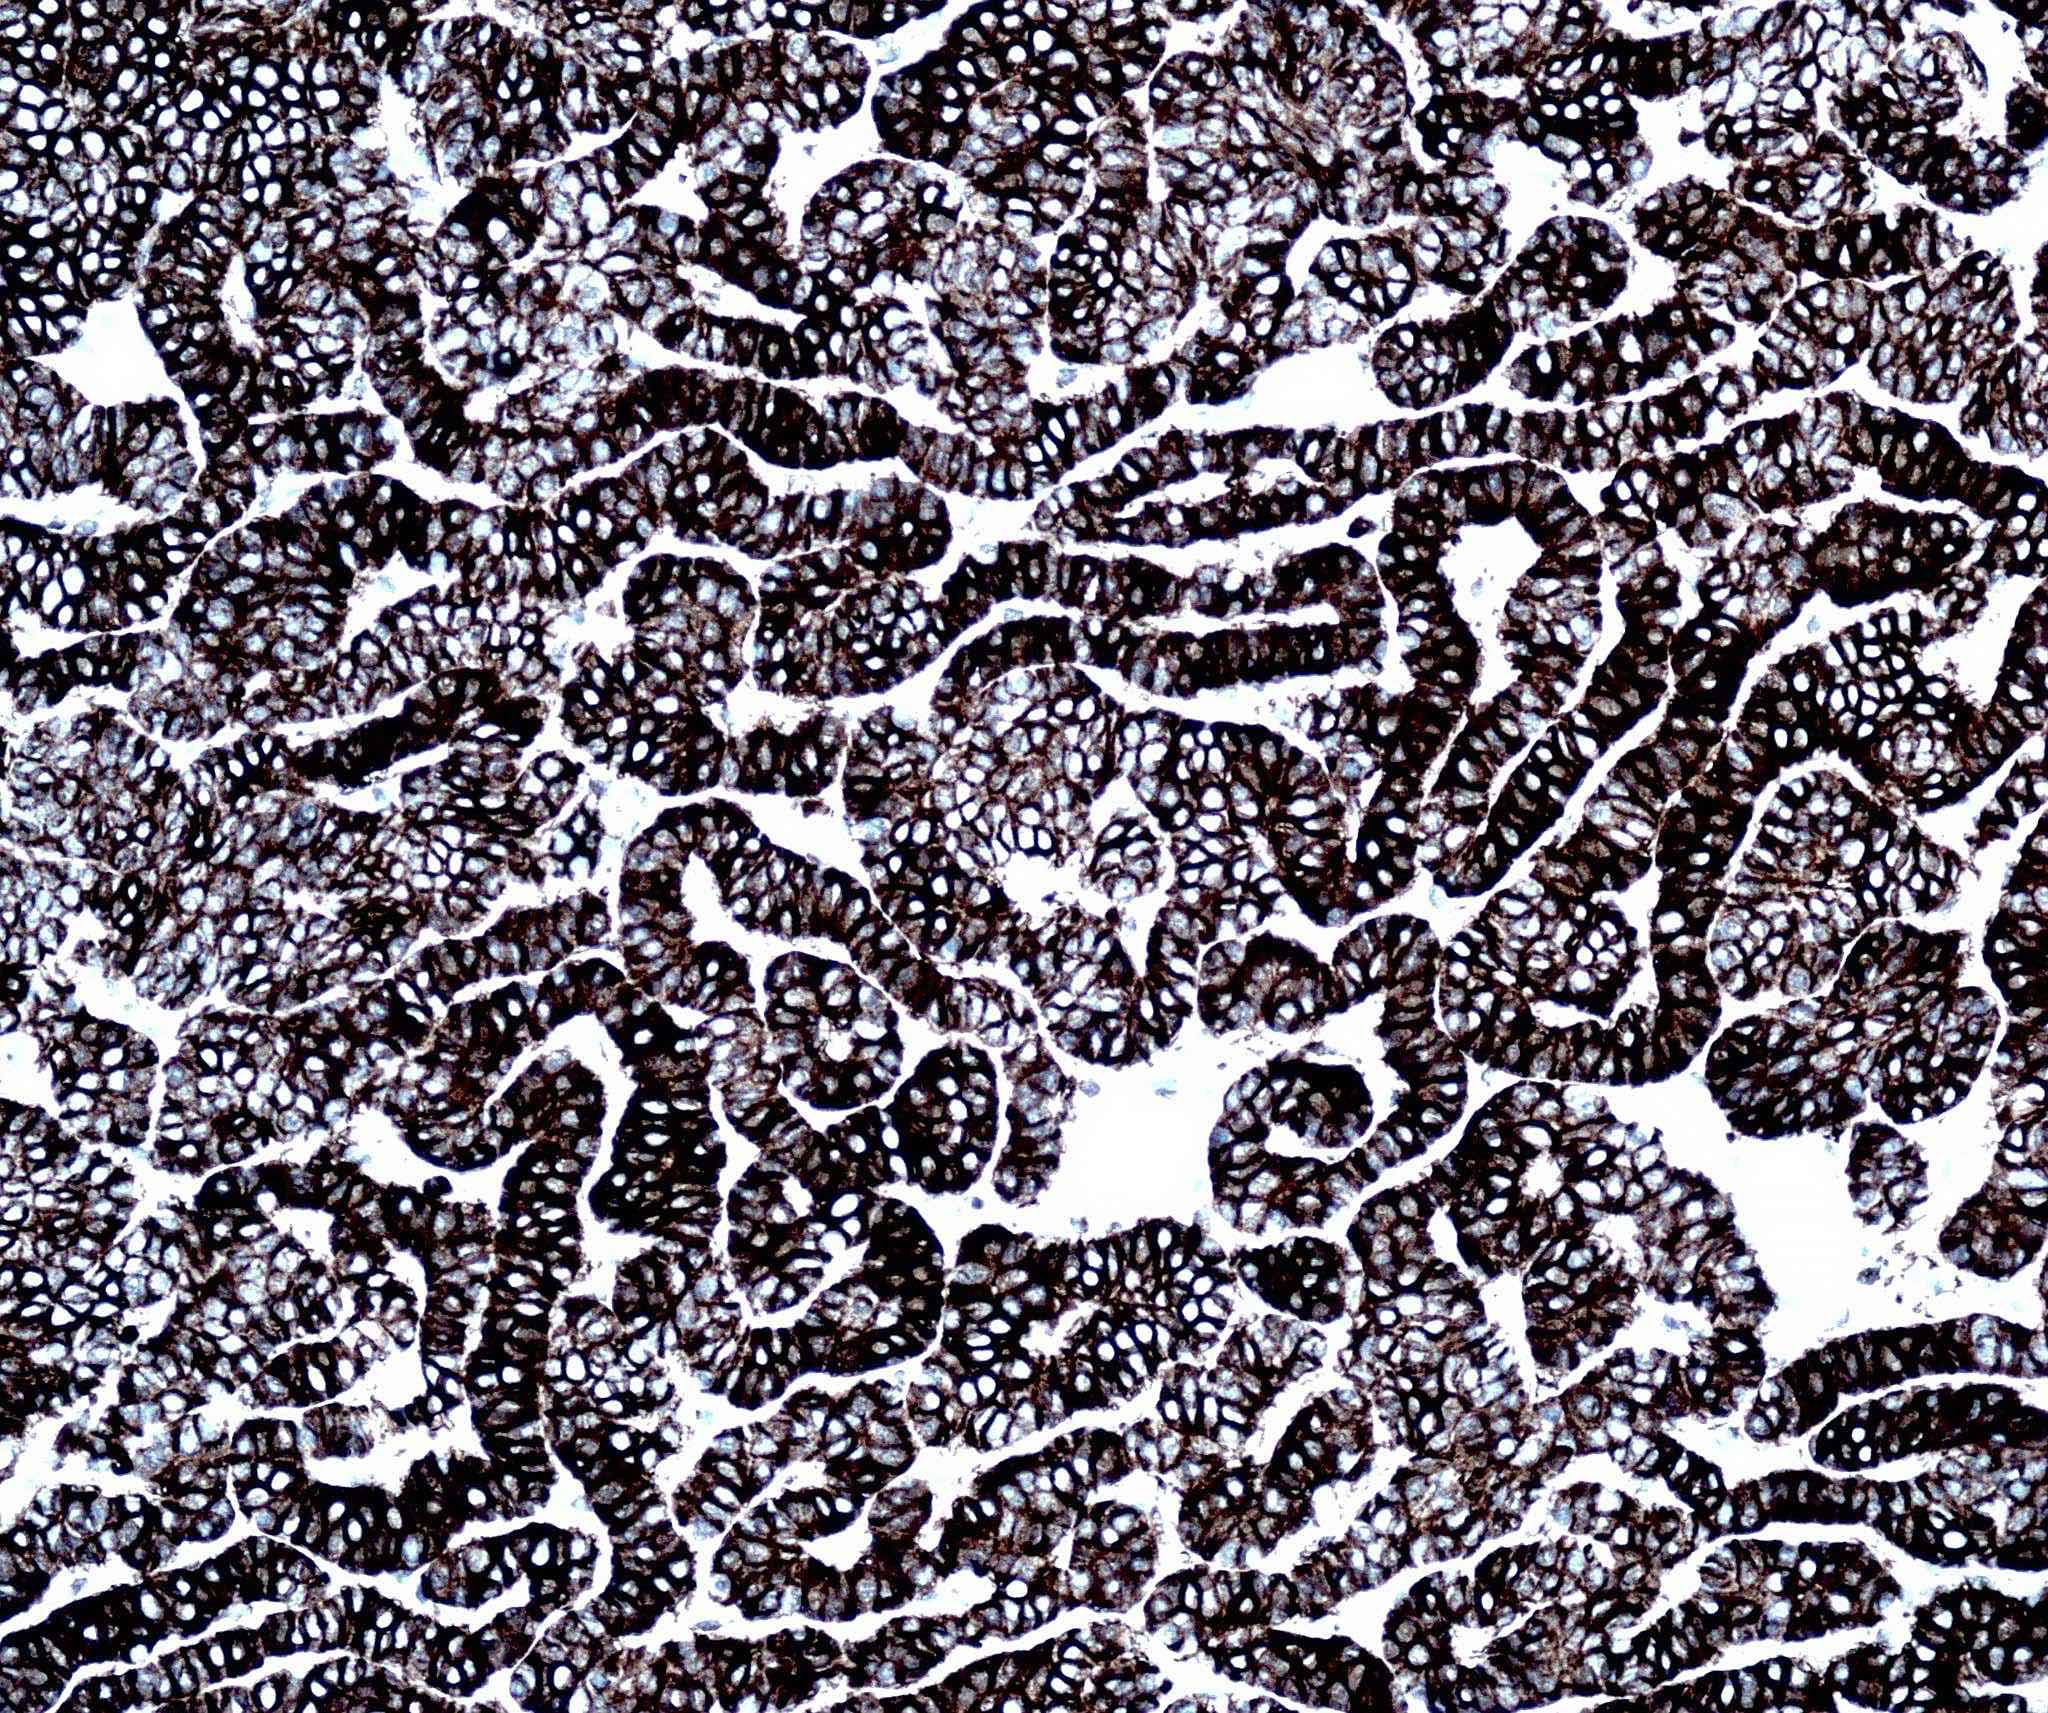

Microscopic (histologic) images

Contributed by Antonina Kalmykova, M.D., Phillip H. McKee, M.D., Sate Hamza, M.D., Eduardo Calonje, M.D.,

Wayne Grayson, M.B.Ch.B., Ph.D., James Sampson, M.B.B.S., M.Sc. and Assia Bassarova, M.D., Ph.D.

Positive stains

- CK AE1 / AE3 (100%), BerEP4 (80 - 100%), p63 (100%), CAM 5.2 (20 - 95%), androgen receptor (33 - 66%), p53 (74.5 - 83%), 34 beta E12 (high molecular weight CK), BCL2 (diffuse pattern), CD10 (positive in tumor cells, negative in stroma) (Dermatopathology (Basel) 2015;2:15, Arch Pathol Lab Med 2017;141:1490, Rom J Morphol Embryol 2018;59:1115, Am J Pathol 1992;141:25)